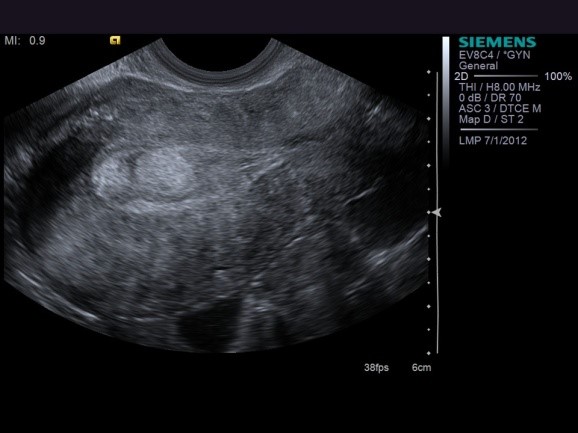

NỘI MẠC TỬ CUNG MỎNG

Nội mạc tử cung dưới 7mm không phải là không thể có thai vì vẫn có một số trường hợp ghi nhận có thai dù nội mạc tử cung rất mỏng. Bên cạnh đó, độ dày đo được trên siêu âm không thể phản ánh hoàn toàn chức năng của nội mạc tử cung. Do đó không thể chắc chắn được rằng với độ dày nội mạc trung bình thì thai sẽ làm tổ. Tỉ lệ làm tổ, thai lâm sàng và thai diễn tiến tăng có ý nghĩa thống kê khi độ dày nội mạc tử cung > 9-10 mm. Độ dày cắt ngang được ghi nhận có thể có thai là 7mm với hình ảnh 3 lá. Độ dày dưới 6 mm làm giảm tỉ lệ thai kỳ sinh đủ tháng. Tuy nhiên hiện tại vẫn chưa rõ nguyên nhân vì sao nội mạc tử cung mỏng lại làm giảm khả năng làm tổ của phôi. Casper cho rằng có thể do nồng độ oxy cao ở lớp đáy nội mạc tử cung có thể bất lợi cho những phản ứng oxygen ở bề mặt nội mạc tử cung.